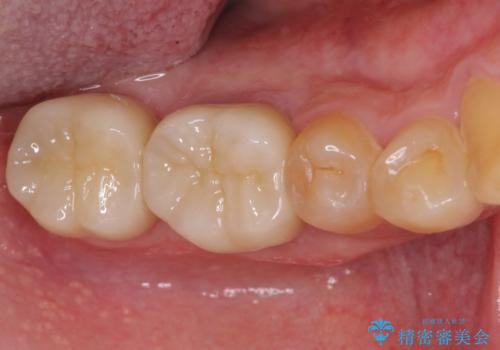

外科処置後の経過を待って、フルジルコニアクラウンにて補綴することとしました。

通っていた歯科医院では、抜歯の可能性が高いと言われていたようですが、何とか健全な状態で歯を保存することができました。